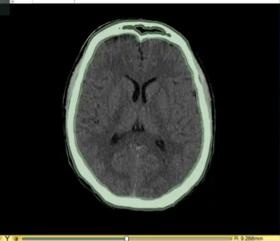

图像分割

该图展示了如何使用3D Slicer来对CT和MR数据中的头骨条纹进行分割。